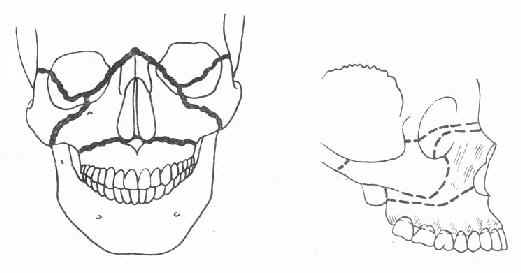

根据解剖结构上的薄弱环节,上颌骨骨折有三种经典类型(图4-12)。第一型骨折(Lefort Ⅰ型骨折)其骨折线通过梨状孔下缘、上颌窦下部,横行到双侧上颌结节;第二型骨折(LeFort Ⅱ型骨折)的骨折线通过鼻骨、泪骨、眶底、颧骨下方,达到上颌骨后壁;第三型骨折(LeFort Ⅲ型骨折)的骨折线也通过鼻骨、泪骨,但横过眶窝及颧骨上方,向后到上颌骨后壁,使上颌骨、颧骨与颅骨完全分离,因此又称为颅面分离。下颌骨是头部唯一能活动的骨骼,在解剖结构上也有它的薄弱部位,如正中颏部、颏孔部、下颌角部及髁状突颈部,这些都是下颌骨骨折的好发部位(图4-13)。下颌骨由于其突出的位置与解剖形态,是颌面部骨折中发生率最高的骨骼。

①正面观②侧面观

图4-12 上颌骨骨折三种类型